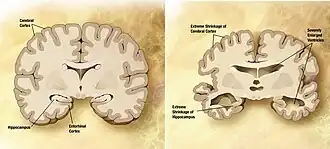

![]() Мозг пожилого человека в норме (слева) и при патологии, вызванной болезнью Альцгеймера (справа), с указанием отличий. | |

Болезнь характеризуется потерей нейронов и синаптических связей в коре головного мозга и определённых субкортикальных областях. Гибель клеток приводит к выраженной атрофии поражённых участков, в том числе к дегенерации височных и теменной долей, участков фронтальной коры и поясной извилины[67].

Как амилоидные бляшки, так и нейрофибриллярные клубки хорошо заметны под микроскопом при посмертном анализе образцов мозга больных[12]. Бляшки представляют собой плотные, в большинстве случаев нерастворимые отложения бета-амилоида и клеточного материала внутри и снаружи нейронов. Внутри нервных клеток они растут, образуя нерастворимые закрученные сплетения волокон, часто называемые клубками. У многих пожилых людей в мозге образуется некоторое количество бляшек и клубков, однако при болезни Альцгеймера их больше в определённых участках мозга, таких как височные доли[93].